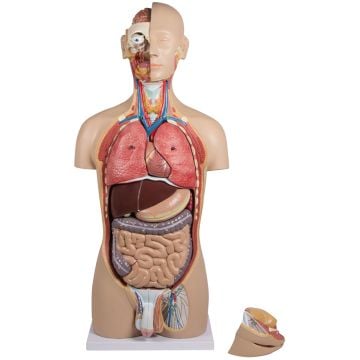

Anatomical Models

Anatomical models as teaching aids

Anatomical and medical models are perfect teaching aids to show and explain the different structures of the human body and the different functions of the joints, muscles, vertebrae, etc.

Medical students and trainees in health care as well as doctors, professors, lecturers, physiotherapists and many health service providers work with the various anatomical models. Due to the realistic, human and life-size presentation, the added value of these medical models is particularly great. As a teaching aid, the anatomy models help enormously to understand the structure and functions of the human body. As part of patient education, the models help the treating doctor or therapist to clearly explain the symptoms and the subsequent treatment to his patient. The visual demonstration helps the patient to understand the important details and thus promotes the relationship of trust between the doctor or therapist and the patient.

Our anatomical models are casts of real samples that are manufactured in accordance with medical quality standards. This gives you models made of high-quality materials that are not only helpful, but also very durable.

In our Kübler Sport range you will find the following anatomical models: